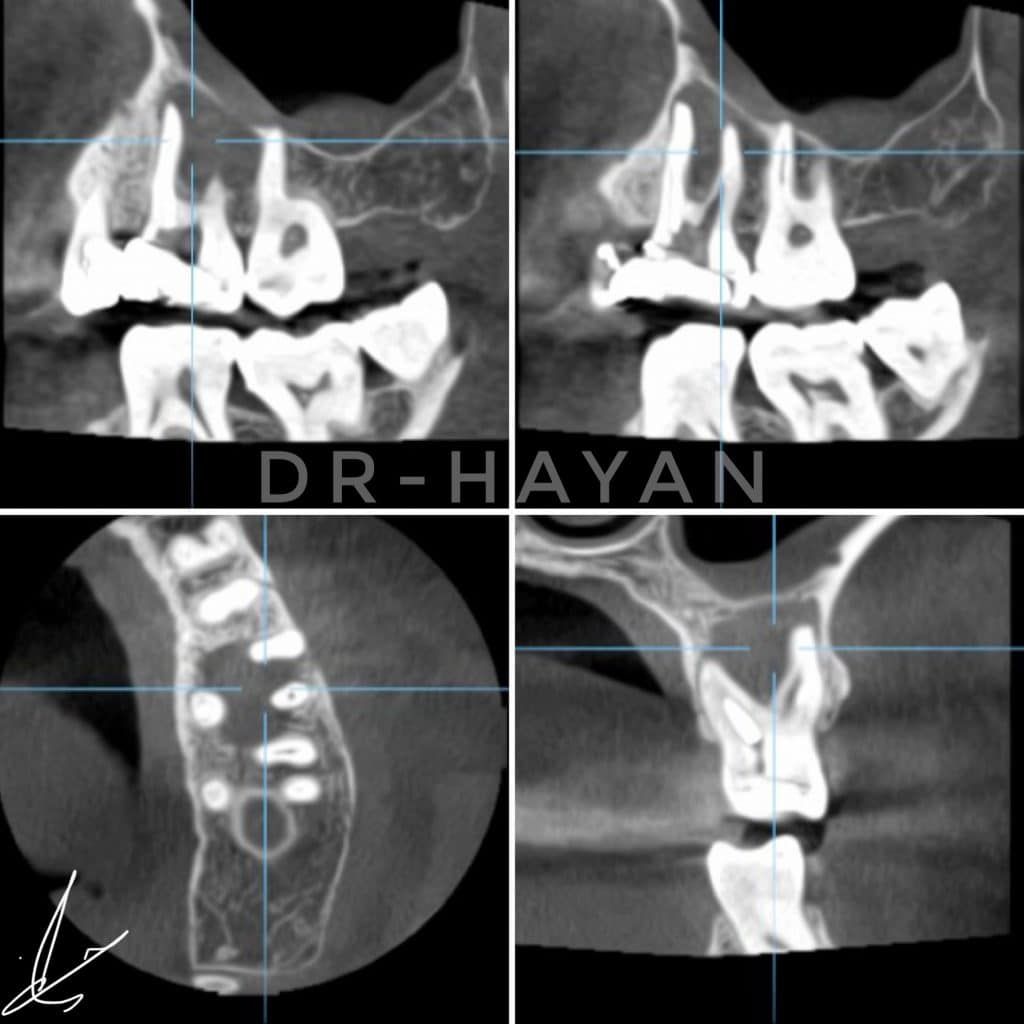

Initial view : 27 years old man suffered from sharp pain related to upper posterior area

CBCT Showing large peri apical lesion related to bad endodontic treatment upper 6 and missing mb2

Peri apical x-ray